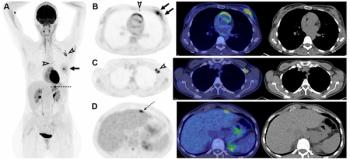

PSMA PET/CT Facilitates Better Long-Term Survival Rates After Salvage Radiotherapy for Recurrent PCa

Patient with biochemical recurrence of prostate cancer who had PSMA PET/CT prior to salvage radiotherapy had better survival rates at one, two and five years, according to newly published research.